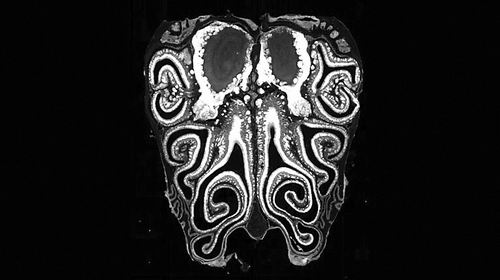

小鼠鼻腔的显微镜横截面图像,显示了鼻腔上皮的解剖结构。图片来源:Datta Lab

在研究中,科学家对来自数百只小鼠的约500万个神经元进行了检测。他们首先通过单细胞测序确定了由鼻腔神经元表达的嗅觉受体,然后利用空间转录组学绘制了关键基因的表达位置图谱。研究人员由此确定了这些受体的位置,并证明它们总是以从鼻腔顶部延伸至底部的水平条纹形式排列。

“每个受体在鼻腔中都占据一个特定的位置。鼻腔中有上千个位置,每个受体基本上都会在一个条带中表达,而这些受体条纹会与其他条纹发生重叠,最终形成上千个相互交错的条纹。”论文共同作者、美国哈佛医学院的Sandeep Robert Datta说。

Datta和同事提出,这种空间定位机制是在发育过程中形成的,并由一系列基因控制。他们发现,一种名为视黄酸的分子在这一过程中发挥了关键作用,且鼻腔不同部位的视黄酸含量存在梯度差异。通过调整这种分子的表达量,科学家证明视黄酸有助于调控基因活性,引导每个神经元根据所处的位置表达正确类型的嗅觉受体。